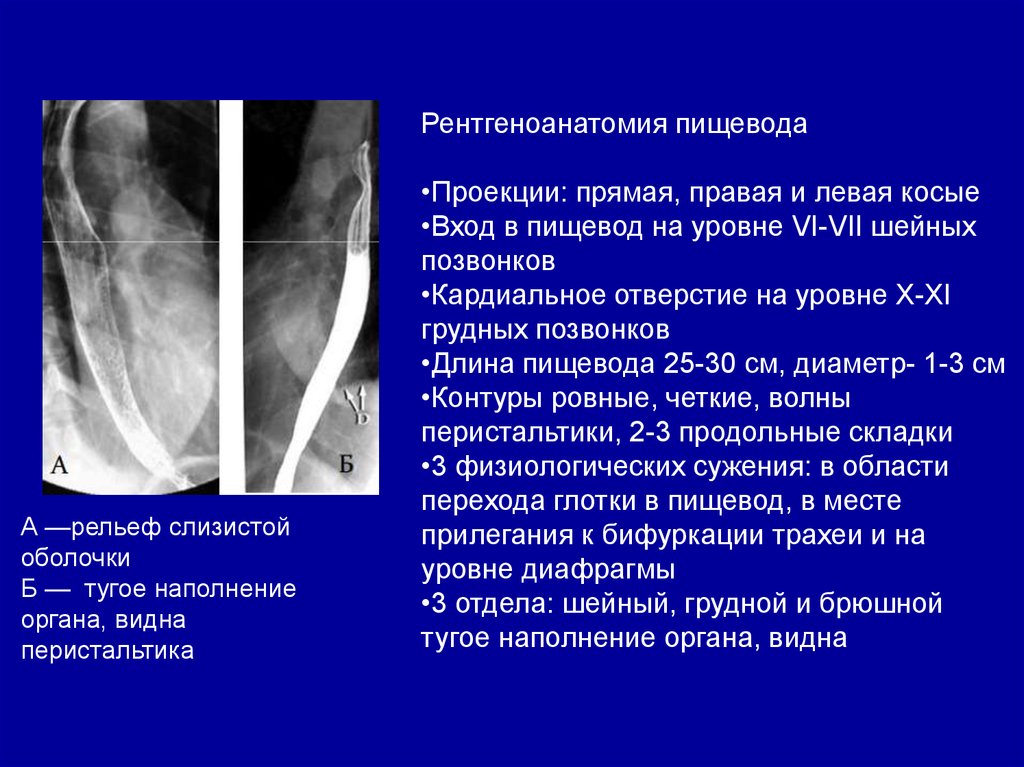

Рентген (рентгеноскопия) желудка, пищевода с барием: что показывает, подготовка

Грыжа пищеводного отверстия диафрагмы и обзор пищевода